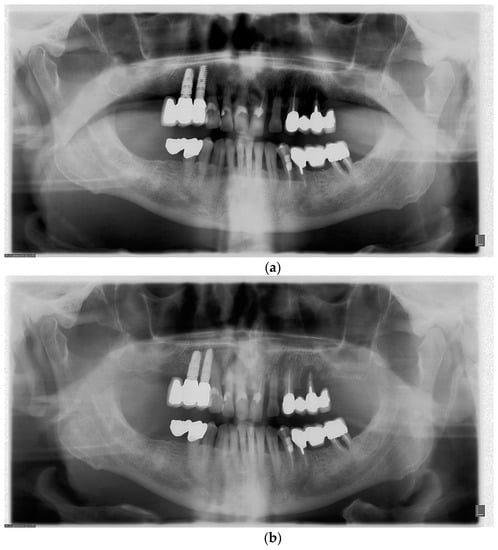

5. The Importance of Head Orientation

6.1. Symmetry

6.2. Inclination of the Occlusal Plane

6.3. Localization of Mandibular Condyles